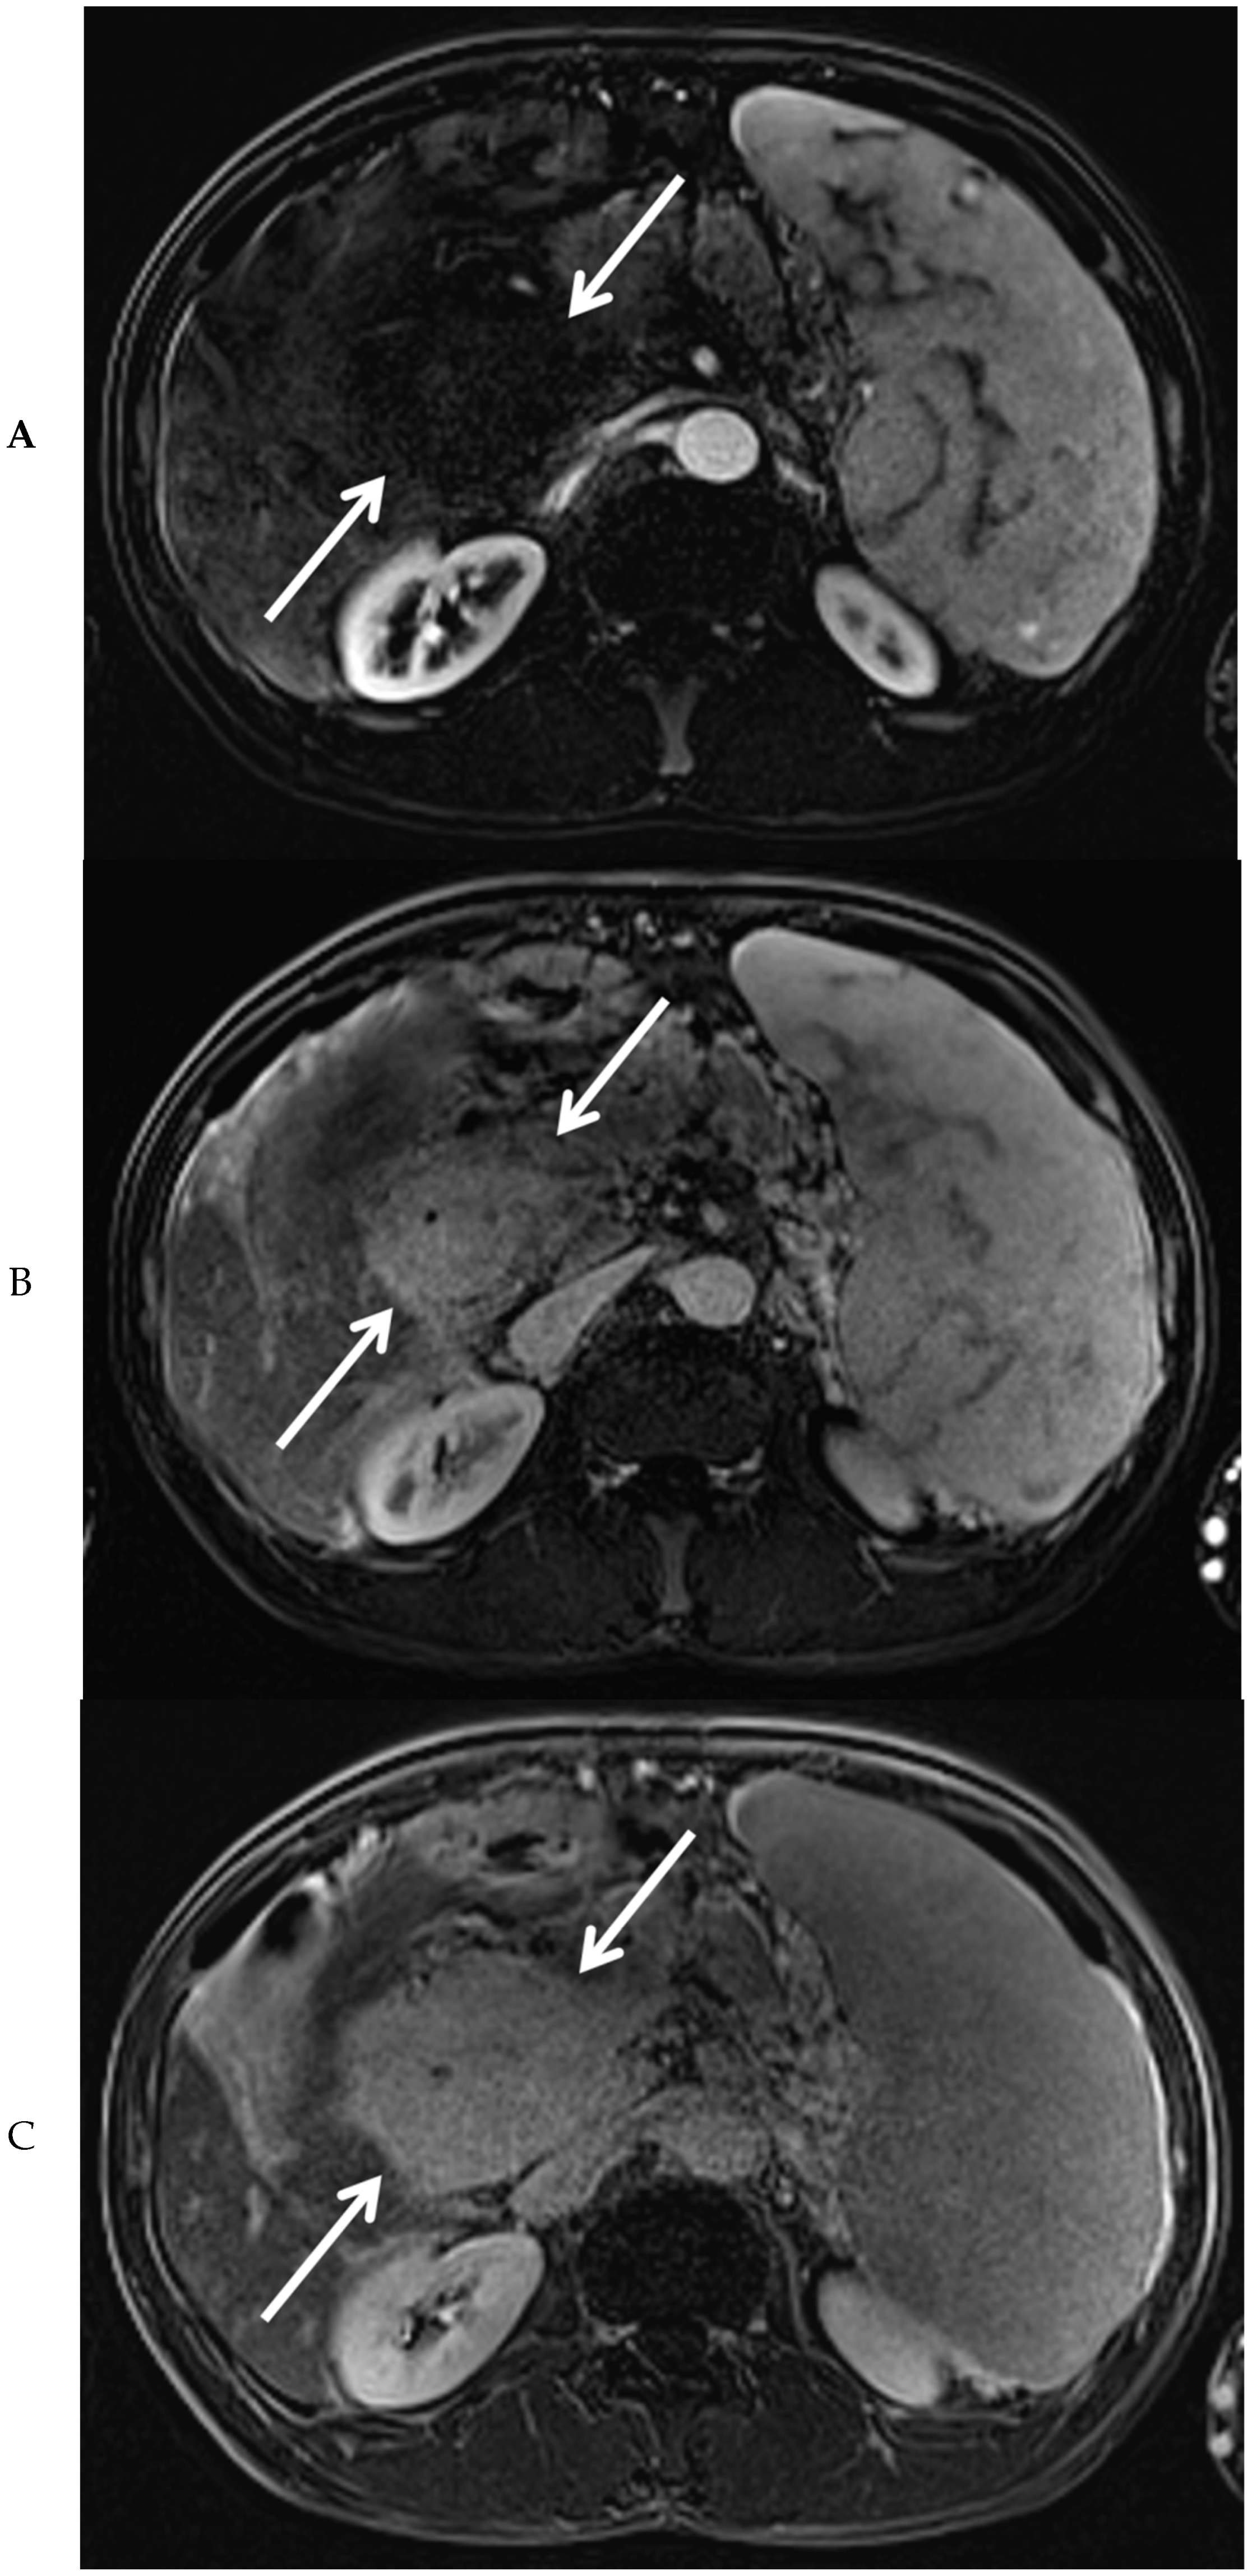

Subsequently, EUS combined with fine needle biopsy, and MRI of the upper abdomen were performed. EUS showed a highly vascular mass with a benign aspect. EUS-guided fine needle biopsy was somewhat difficult due to hardness of the mass. The histopathologic findings were most consistent with a lesion of vascular origin, such as hemangioma. MRI of the upper abdomen revealed a large mass surrounding the common bile duct, central intrahepatic bile ducts, cystic duct, and gallbladder, without diffusion restriction. After administration of intravenous contrast medium, no enhancement of the mass was visible in the arterial phase (Figure 3A). However, many small vessels were visible within the mass in the portal venous phase (Figure 3B), with diffuse homogeneous enhancement of the mass in the delayed phase (Figure 3C). At the MRCP, narrowing of the common bile duct was visible along its complete course, combined with dilation of the intrahepatic bile ducts (Figure 3D). At T2-weighted imaging, the mass around the narrowed common bile duct was slightly hyperintense when compared to the liver parenchyma (Figure 3E).

Figure 3. Magnetic resonance imaging of the mass in the upper abdomen (arrows). Shown are T1 weighted subtraction images of the mass in the upper abdomen with fat suppression after administration of intravenous contrast medium in the arterial (A), portal venous (B), and delayed phase (C). At magnetic resonance cholangiopancreaticography, narrowing of the common bile duct is visible along its complete course (arrows), combined with dilation of the intrahepatic bile ducts (arrowheads) (D). At T2-weighted imaging (E, coronal view), the mass surrounding the narrowed common bile duct was slightly hyperintense, when compared to the liver parenchyma (arrows).